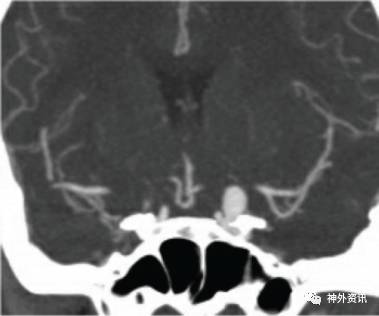

图1. 冠状位CT血管成像,可见左侧眼动脉瘤瘤颈而非瘤顶已侵蚀部分前床突,须行前床突切除术来暴露瘤颈。